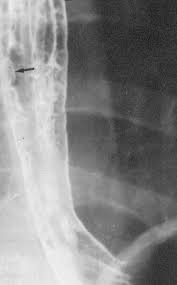

The Shaggy Esophagus Springerlink

The Shaggy Esophagus Springerlink from media.springernature.com

Behr j, kreuter m, hoeper mm, wirtz h, klotsche j, koschel d, andreas s, claussen m, grohé c, wilkens h, randerath w, skowasch d, meyer fj, kirschner j. A recent review reveals 56 documented cases in the literature. Animals with mild esophagitis generally have a favorable prognosis. B from levine ms, woldenberg r, herlinger h, et al. Esophagitis may cause odynophagia and even esophageal hemorrhage, which is usually occult but can be massive. Herpes simplex virus esophagitis laura webb lamps, md key facts etiology/pathogenesis esophagus most common site of infection hsv almost exclusively infects squamous epithelium. Department of radiology of the loyola university medical center, usa. Hsv esophagitis has been described in immunocompetent hosts, however, it remains a rare entity.